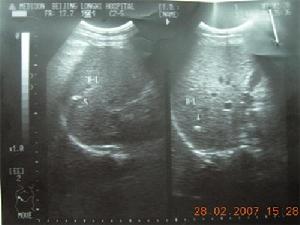

膽結石超聲片(三)血尿 結石移動擦傷腎盂和輸尿管黏膜,引起鏡下或肉眼血尿,多與疼痛同時發生。約20%~25%患者結石排出時無血尿。

B型超音波檢查能診斷出X線陰性結石,當結石直徑>0.5cm時即可顯示,其缺點是細小結石常易漏診,且不能作為手術定位。